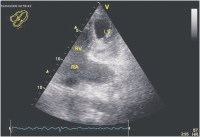

Echokardiographie aktuell: Tubuläre Struktur im Bereich des Sulcus atrioventricularis links bei 2 Patienten

Journal für Kardiologie - Austrian Journal of Cardiology 2009; 16 (1-2): 46-47 Volltext (PDF) Abbildungen mit Filmsequenzen